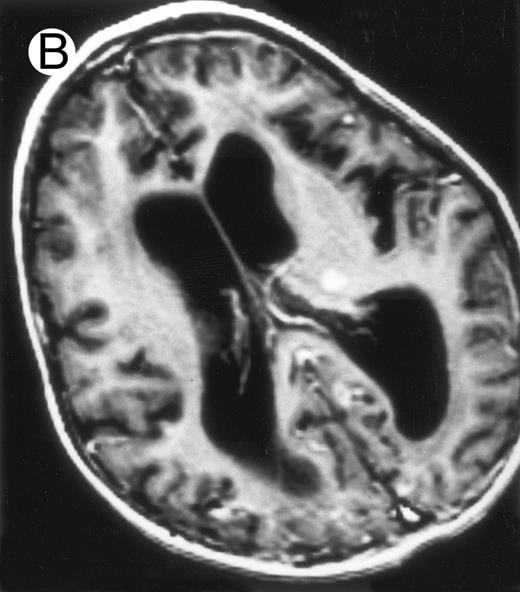

Three different aspects of brain imaging in HLH patients. (A) CT scan of a 3-month-old baby showing a large subdural effusion, several necrotic areas and hypodensities of the white matter. (B) Brain magnetic resonance of a 14-month-old boy showing large confluent areas of hypersignal in T2-weighted images. (C) Large symmetrical necrotic areas of cerebellar white matter in a 41/2-year-old girl (MRI).

Among the nine children with initial neurological symptoms, seizures were the most frequent initial symptom in the youngest patients, whereas ataxia was found in the two oldest patients (46 and 58 months old, respectively) (Table 1). All nine patients had the same CSF abnormalities as patients with meningitis only. Eight of these nine patients had a neuroradiological study performed at the time of their first neurological symptoms (Table 1). The two most frequent lesions were focal necrosis with parenchymal volume loss and atrophy (Fig 2A and C) and white matter abnormalities (Fig 2B). Several small focal lesions with hypersignal at MR imaging that enhanced after administration of gadopentate dimeglumine (or contrast on CT scan) were also observed in two cases.

Together, 19 patients had primary severe CNS disease progression or CNS relapse (Fig 1). Three of 19 had a CNS relapse characterized by meningitis only. Neurological symptoms occurred in 16 of these 19 patients (9 from the onset and 7 after the initial meningitis) (Fig 1). No clinical or neuroradiological difference was detected between the patients who developed neurological symptoms as the initial CNS manifestation or after initial meningitis (Table 1). The occurrence of these neurological manifestations marked a turning point in the evolution of the disease, as chemotherapy led to an improvement of the neurological symptoms in only three patients despite the use of intensive treatment by MTX IT. In these three patients, neurological sequelae persisted after the first symptoms and a relapse occurred within 3 to 10 months. Brain imaging was repeated during chemotherapy for four patients with progression of the CNS disease: in three patients, a severe brain atrophy developed (Fig 3A and B) and in the last patient who initially had contrast enhancement in cerebellar white matter, a cerebellum parenchymal loss was observed (Fig 2C). All of these 19 patients treated by chemotherapy only (n = 15) died during a last episode of coma and brain stem symptoms associated with a systemic hemophagocytic syndrome, 6 ± 6 months after the first neurological symptom (irrespective of the age at this first event). Four of these 19 patients were transplanted (one patient received an HLA-identical BMT, three an HLA-partially identical BMT). Median delay between diagnosis and BMT was 14 months (range, 2 to 20 months). All of these four patients died of BMT-related toxicity and/or disease progression.